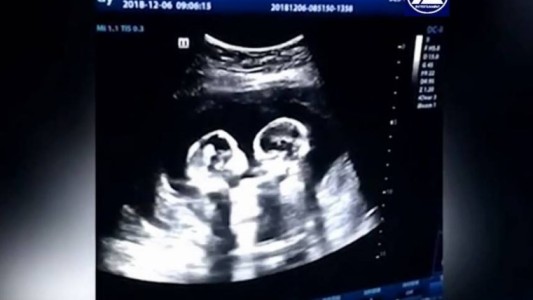

Misterio en Estados Unidos: pensó que tenía piedras en el riñón, fue al hospital y dio a luz a una nena